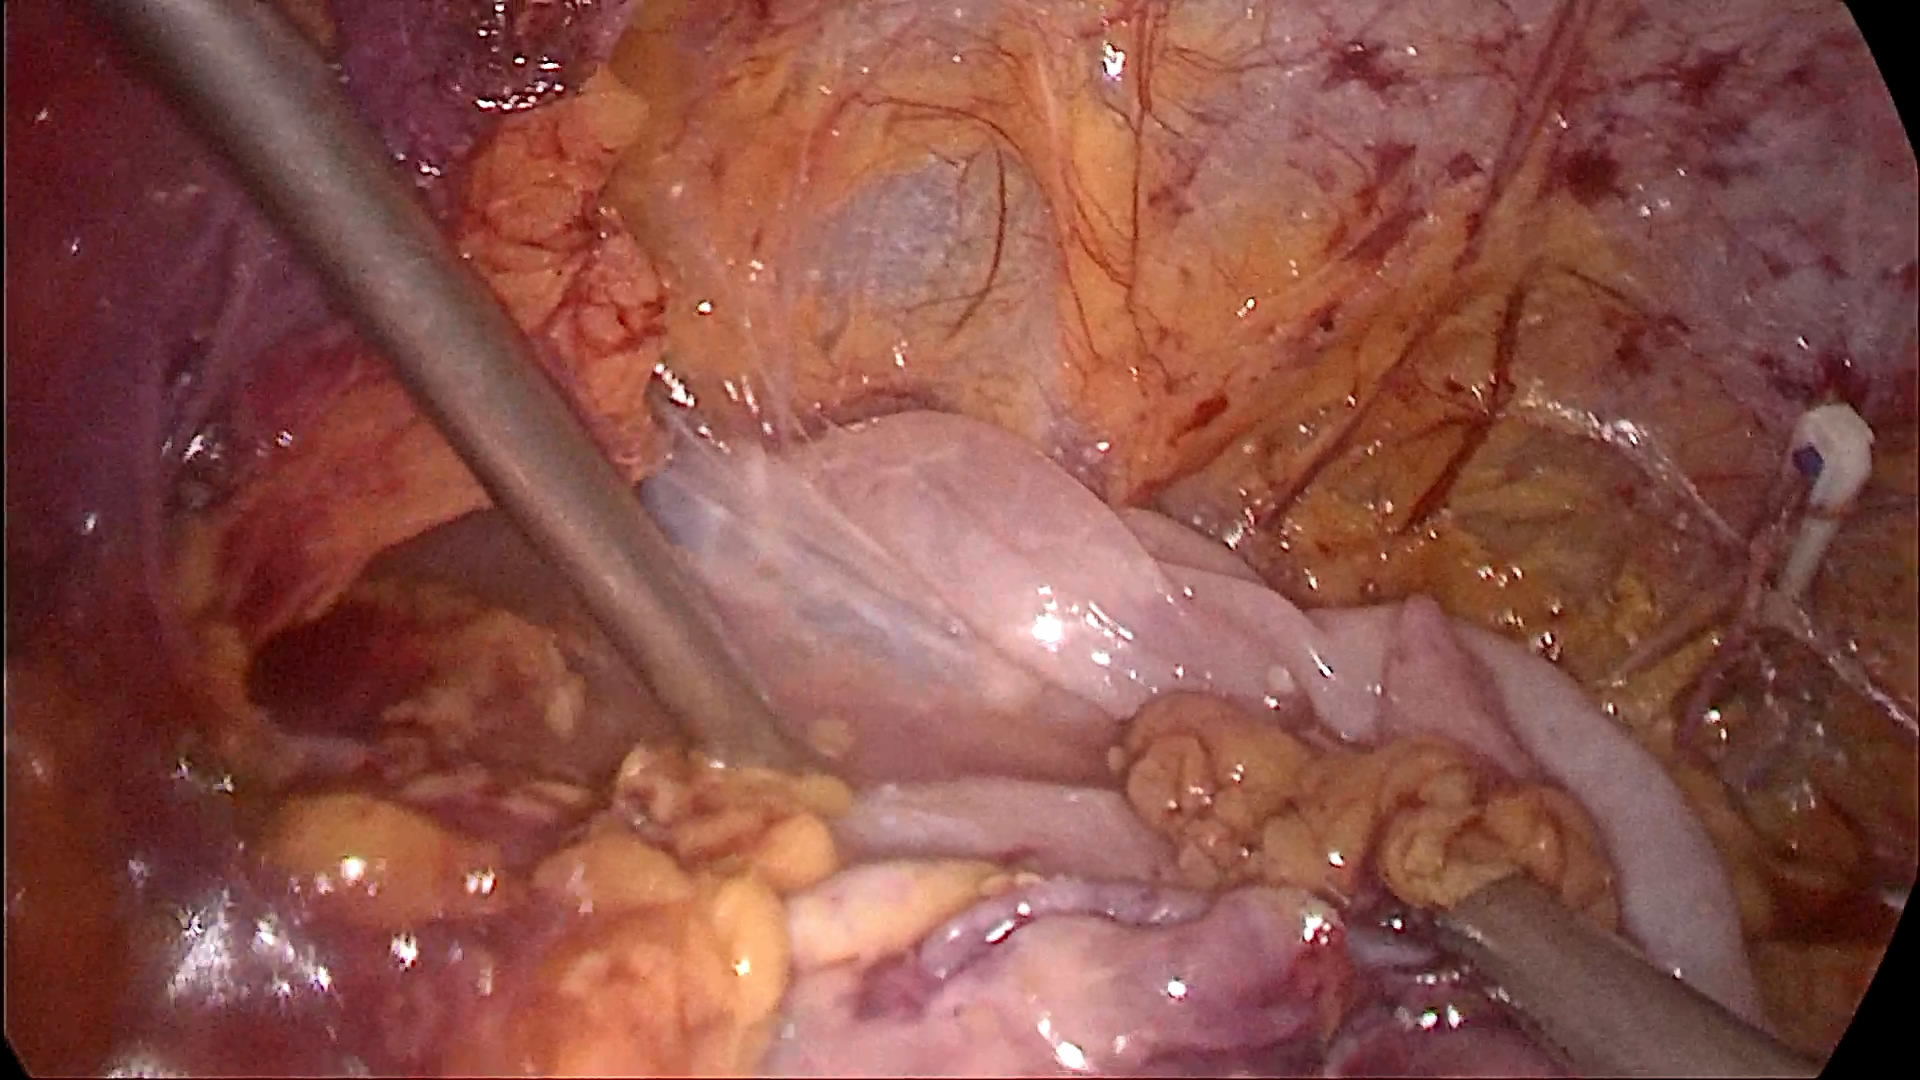

双侧输尿管切开取石术+双侧输尿管裁剪成型术,术中见上段输尿管因梗阻扩张似肠管,与周围脏器黏连明显,输尿管切开见结石周围包裹息肉,取石钳完整取出结石,双侧输尿管裁剪成型并留置内支架支撑。

正常人输尿管长约25cm左右,该患者输尿管迂曲扩张,长达35-40cm左右,裁剪部分输尿管成型